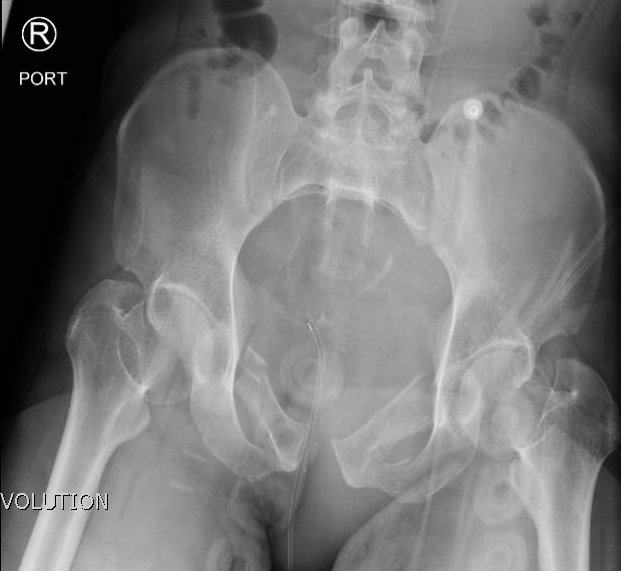

Open Book Pelvic Fracture

A 31-year-old male was brought in by paramedics status post high-speed motorcycle collision. The patient was tachycardic and hypotensive with an initial Glascow coma scale (GCS) of 11. He required immediate blood transfusion and intubation. The patient had multiple traumatic injuries including a deformity to the left thigh and an unstable pelvis. He had palpable distal pulses, and grossly normal sensation and motor function to his bilateral lower extremities.

The initial radiograph of the pelvis shows an open-book pelvic fracture deformity with pubic symphyseal dislocation, left greater than right sacroiliac diastases, and fractures of the left superior and inferior pubic rami, right inferior pubic ramus, and left acetabular anterior column. The additional inlet and outlet radiographs of the pelvis after application of a pelvic binder also show an open book fracture with significant improvement of the widened pubic symphysis.

Severe pelvic injuries, including open book dislocations, have a high mortality rate of 10.4%.1,2 The mechanism is commonly a motor vehicle collision or fall from a significant height.3 Open book dislocations of the pubic symphysis are rare, representing 0.3–8.2% of all fractures,4,5 and can lead to fatal complications through vascular, abdominal, and nervous injuries.6 In severe pelvic traumas, pelvic binders must be applied as soon as possible to reduce bleeding by realigning fracture surfaces and provide stabilization of unstable fractures.7,8 Open book dislocation can be identified via plain anteroposterior pelvis radiographs.9 Definitive treatment of open book dislocations are highly individualized and come secondary to controlling hemorrhagic bleeding. The most common method is open reduction and internal fixation (ORIF) although in some cases, external fixation can be sufficient to stabilize the pelvis.10 Our patient was admitted for multiple traumatic injuries and underwent closed reduction and percutaneous fixation of posterior pelvic ring, including bilateral sacroiliac joints, and ORIF of the pubic symphysis.